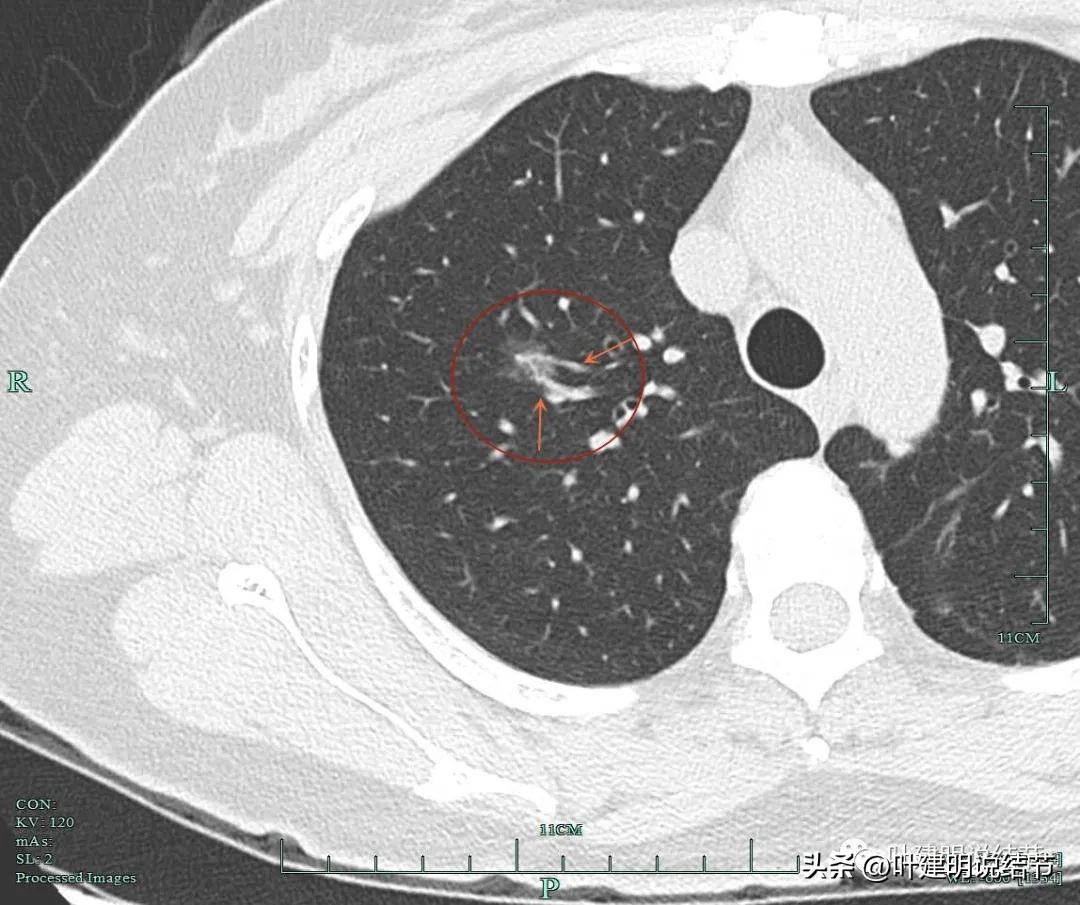

显示微血管进入以及灶内血管异常增粗,成分病灶内的实性成分。表面不平有毛刺。黄色箭头所示还有支气管截断的样子。

显示血管弯征,

显示明显毛刺。

显示典型的混合磨玻璃密度以及表面不平毛刺。

细支气管扩张导致的空泡征。

显示典型的血管穿行以及灶内血管壁散开来,管壁受到破坏或影响,成为虫蚀样。